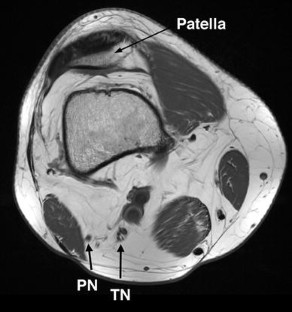

Clinical trial design in amyotrophic lateral sclerosis (ALS) remains hampered by a lack of reliable and sensitive biomarkers of disease progression. The present study evaluated peripheral nerve diffusion tensor imaging (DTI) as a surrogate marker of axonal degeneration in ALS. Longitudinal studies were undertaken in 21 ALS patients studied at 0 and 3 months, and 19 patients at 0, 3 and 6 months, with results compared to 13 age-matched controls. Imaging metrics were correlated across a range of functional assessments including amyotrophic lateral sclerosis functional rating scale revised (ALSFRS-R), lower limb muscle strength (Medical Research Council sum score, MRCSS-LL), compound muscle action potential amplitudes and motor unit number estimation (MUNE). Fractional anisotropy was reduced at baseline in ALS patients in the tibial (p < 0.05), and peroneal nerve (p < 0.05). Fractional anisotropy and axial diffusivity declined in the tibial nerve between baselines, 3- and 6-month scans (p < 0.01). From a functional perspective, ALSFRS-R correlated with fractional anisotropy values from tibial (R = 0.75, p < 0.001) and peroneal nerves (R = 0.52, p = 0.001). Similarly, peroneal nerve MUNE values correlated with fractional anisotropy values from the tibial (R = 0.48, p = 0.002) and peroneal nerve (R = 0.39, p = 0.01). There were correlations between the change in ALSFRS-R and tibial nerve axial diffusivity (R = 0.38, p = 0.02) and the change in MRCSS-LL and peroneal nerve fractional anisotropy (R = 0.44, p = 0.009). In conclusion, this study has demonstrated that some peripheral nerve DTI metrics are sensitive to axonal degeneration in ALS. Further, that DTI metrics correlated with measures of functional disability, strength and neurophysiological measures of lower motor neuron loss.